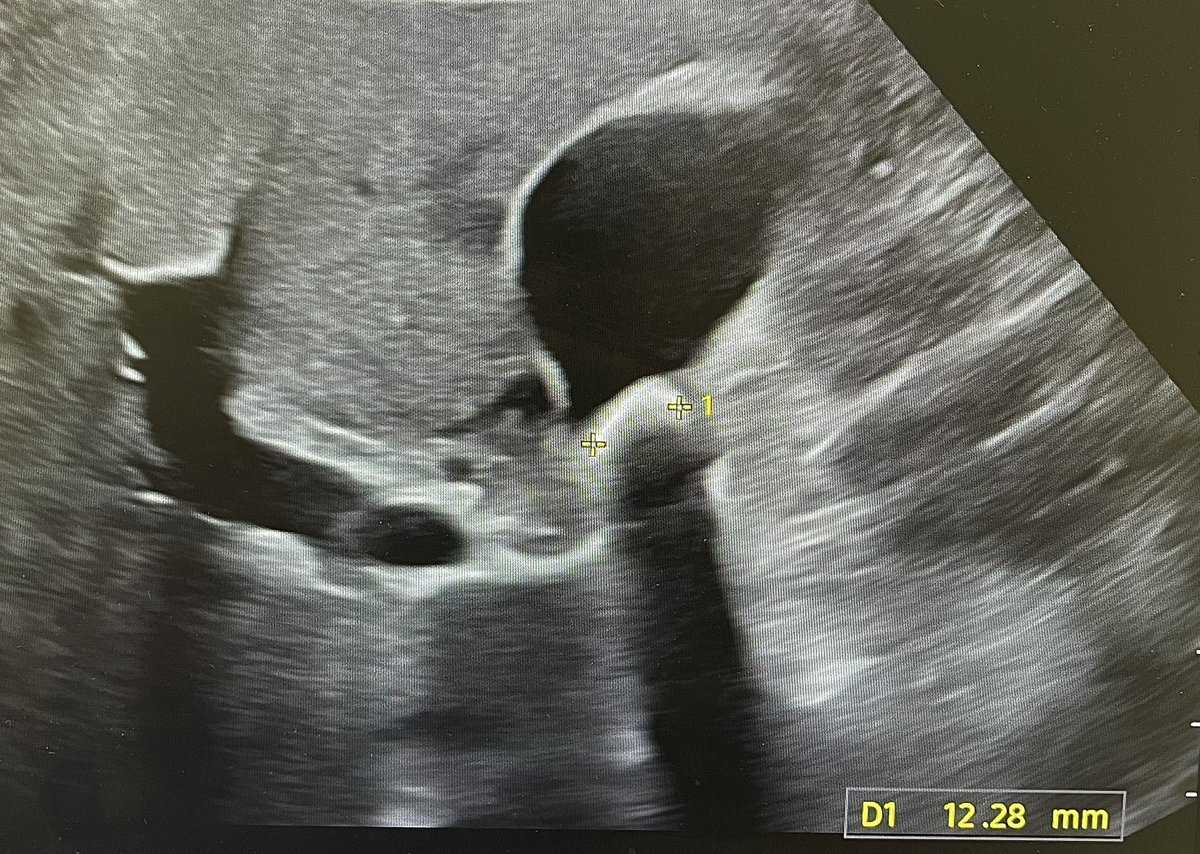

@DeeloOfficial

Deelo

3 days

Corpus luteum cysts are physiological. Normal variants. Repeat scans are not required. @Rad_Munagi